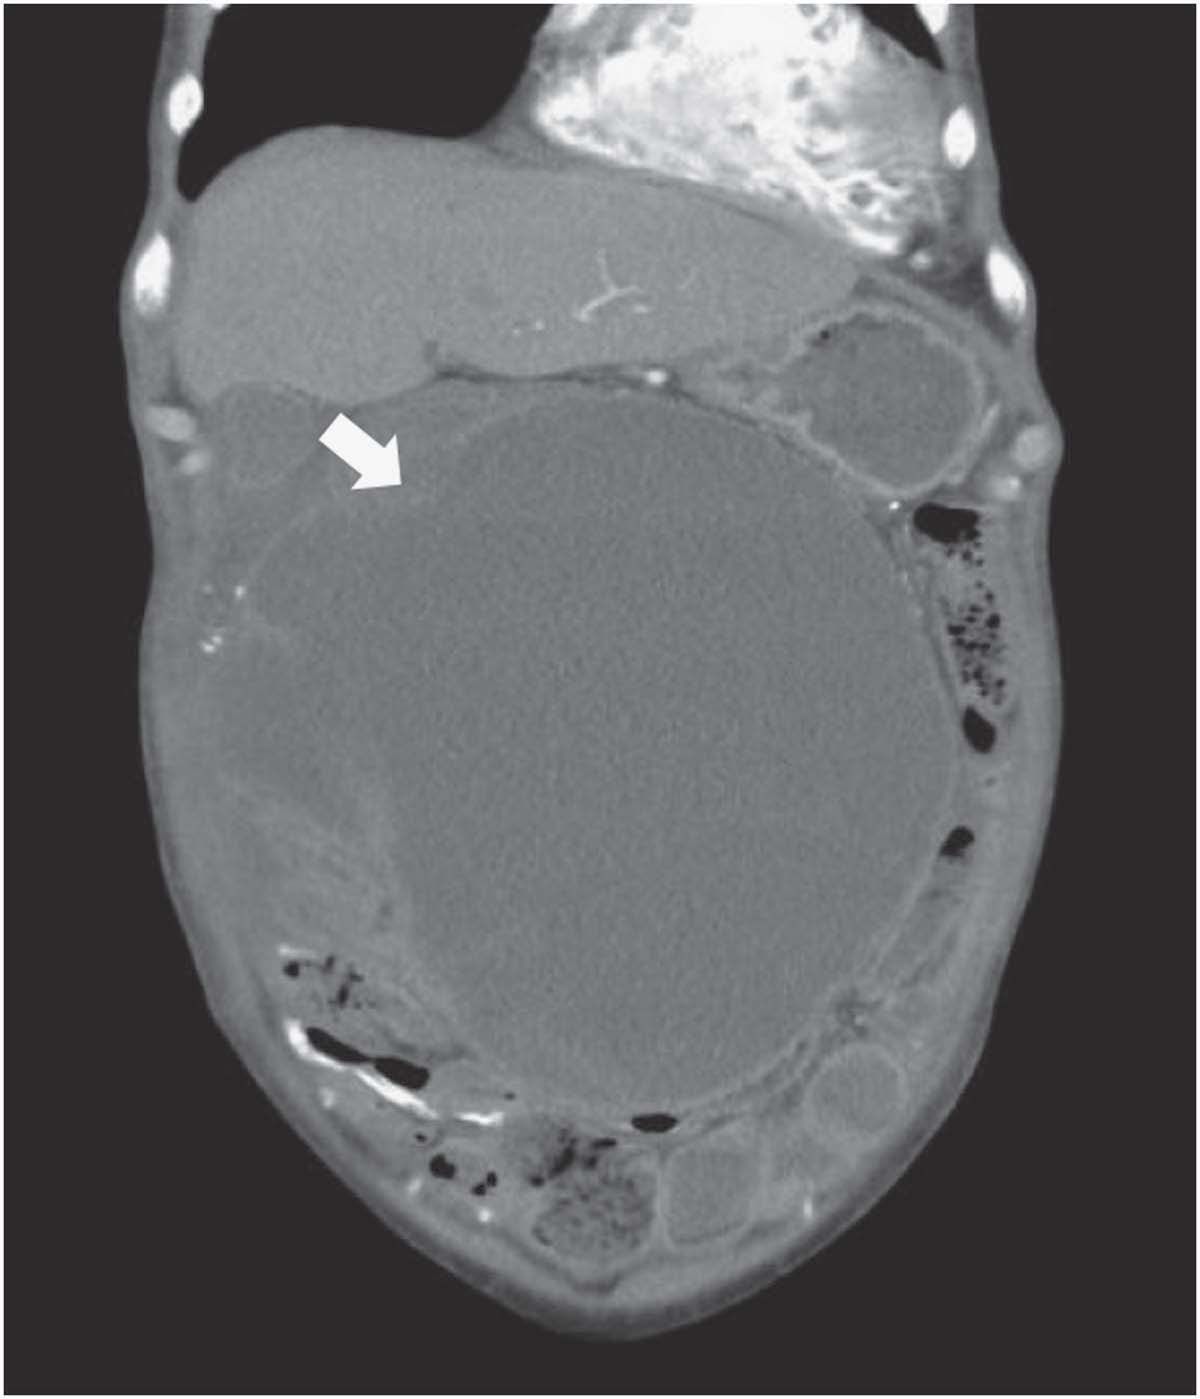

revealed normal blood leukocyte count (WBC: 7,100/mm3 ) but an elevated C-reactive protein level (50.3 mg/l). An abdominal radiograph was obtained to evaluate his symptoms. The intestinal wall was outlined by continuous calcifications (Figure 1 , arrows), and the curvilinear calcification on the right side of the radiograph was peritoneal calcification (Figure 1, white arrows). A contrast enhanced

computed tomography scan demonstrated fluid within the abdomen surrounded by thickened, enhancing peritoneum. The adherent bowel loops were collected centrally by the encapsulating calcified peritoneum, supporting the diagnosis of EPS (Figure 2, white

arrows).